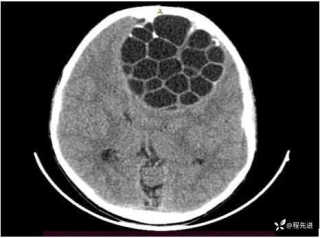

灼见|如果是你,如何处置山东男孩(多器官切除病例)

文/西地兰 特别声明:所有观点仅代表个人言论 特别声明:与当事双方均无利益相关 山东男孩,目前全网沸沸扬扬,看过一些观点,直言不讳地说,大多偏颇。要么一股脑地指责医方的全责,甚至有说千万别在县医院看病。要么又为医方无休止的遮羞,认为这样的手术在县医院做下来已经非常了不起。而我想到的是,以后面临类似的病例,我们怎么办?那么我们不如来一次专业的病案讨论。既然是事后讨论,难免有事后诸葛亮的感觉,但是假如下一次,同行们遭遇这样的病例,如何处置?这是医疗行业所面临的问题。希望我整理的这些思路和相关病例,对同行们有所帮助!就目前的资讯外界不足以判断是否需要急诊,如果需要急诊,那么只能根据术中所见进行处理,

目前知道的消息,第一,术前发现一个血肿,然后做增强CT发现一个占位,没说血肿与肿瘤的关系,术后病理没有描述肿瘤出现破裂出血,大概率就一个小血肿,我就不明白当地主任凭哪个指针去给这小孩开急诊刀的?哪个指南告诉他需要急诊开?第二,诊断不明确他想的不是进一步检查,一边观察一边进一步查,他反而选择腹腔镜探查,这个探查的指针在哪?第三,腹腔一个血肿,没有活动性出血,没有血压心率出现问题,为什么要开腹进去碰它?不能等血肿吸收再明确肿瘤性质吗?第四,1点进腹,3点病理结果出来,按这个时间还算顺利,应该还没出事,孩子还算平稳,病理是低度恶性,切了就治愈,他一年能开几台这手术,就敢继续做,拿孩子练手。第五,后面

2023年10月26日,来自山东菏泽市成武县的小烨和他家人的命运被彻底改变了。这个原本阳光、可爱的小男孩在一次意外被撞击后,在医院检查出了腹腔内存在肿瘤,并在手术中被切除了包括十二指肠、胰腺、大部分胃和小肠等多个器官。此后便无法再像正常人一样吃饭、喝水,活着要靠长期静脉注射营养液。一份2024年12月由第三方机构出具的司法鉴定意见书显示,当时给小烨做手术的成武县人民医院在该医疗行为中存在过错,与小烨的损害后果之间存在因果关系,建议医疗过错在损害后果中的原因力大小为同等原因。此外,另一份由成武县卫生健康局在2025年9月28日发出的书面答复中显示,成武县人民医院存在24小时内未完成病历;手术知情